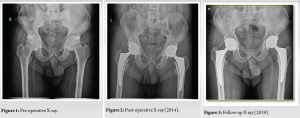

A 56-year-old man who is a known case of ankylosing spondylitis underwent bilateral THA (Fig. 1) for secondary osteoarthritis of both hips in the same sitting in our Hospital, Chennai, Tamil Nadu, India, in 2014. The patient had other comorbidities such as hypertension, hypothyroidism, cholelithiasis, and gastroesophageal reflux disease. Since the patient was young and active, uncemented THA with CoC bearing surface was used. The implant used where a pinnacle titanium shell size 54 with 36 × 54 mm ceramic liner, 36 + 8.5 biolox delta ceramic head (Johnson and Johnson DePuy). On the femoral side, size 4-high off-set titanium trilock femoral stem, which is proximally coated. The inclination of the acetabular cup was 40°, anteversion of the acetabular cup was 22° and stem anteversion was 10° (Fig. 2). The patient was immediately mobilized post-surgery. The patient was on regular follow-up for the initial 4 years up to 2019, his X-ray taken during the 2019 follow-up showed no signs of stem subsidence or lysis and loosening implants (Fig. 3).